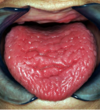

What is this clinical presentation?

Geographic tongue/

areata migrans